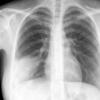

Case 4 RML pneum PA

Date: 04/16/2005

Views: 5852